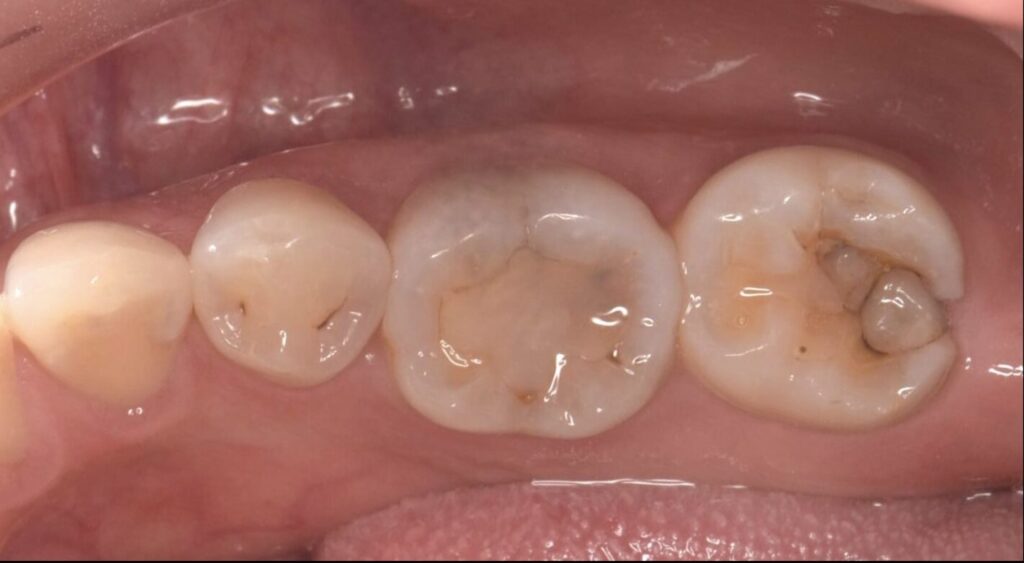

虫歯をセラミックインレー治療した症例

Before

| 治療内容 | セラミックインレー |

| 治療期間・治療回数 | 2回 |

| 治療費用 | 143000円(税込) |

| 備考 | 30代 男性 |